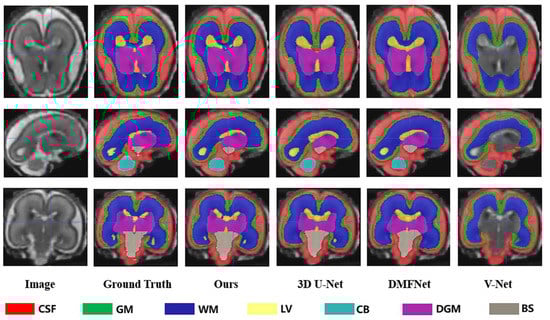

Table 3 showed the evaluation results of several metrics for two different gestational age groups (20–27 GW and 28–35 GW) as a way to analyze the effect of gestational age on the performance of our segmentation algorithm. The results obtained in the table showed that in the 28–35-week group, the segmentation performance of both gray matter and white matter became worse, with a significant decrease in DSC, VS, PRE, and SEN and an increase in HD95. The segmentation of the lateral ventricles was also poorer in the 28–35-week group. This supported our hypothesis that segmentation was more difficult due to the decrease in ventricle-to-brain volume ratio with increasing gestational age. Overall, the 28–35 age group showed a slight increase in segmentation difficulty compared to the group of 20–27 GW, with a 2.15% decrease in mean DSC (%) from 89.88 to 87.95 and a 1.98% decrease in VS (%) from 91.58 to 89.77. We also provided a few examples for visual comparison of the two age groups in Figure 7. The cerebral cortex expanded with increasing gestational age, and the morphology of the cerebral gyri and sulci became more notable. Discernibility of the gray/white matter boundary became variable in some regions due to partial volume effects produced by gyri. Gray matter (green) segmentation became more indistinguishable from cerebrospinal fluid (red) and white matter (dark blue) boundaries. In the 28–35 GW group, the volume of ventricles (yellow) became significantly smaller and the shape changed, and it was no longer simply vesicular or bicornuate, which also led to an increase in the random error of segmentation.

Figure 7.

Segmentation results of different gestational age groups (20–27 weeks and 28–35 weeks) in axial, sagittal and coronal planes respectively.